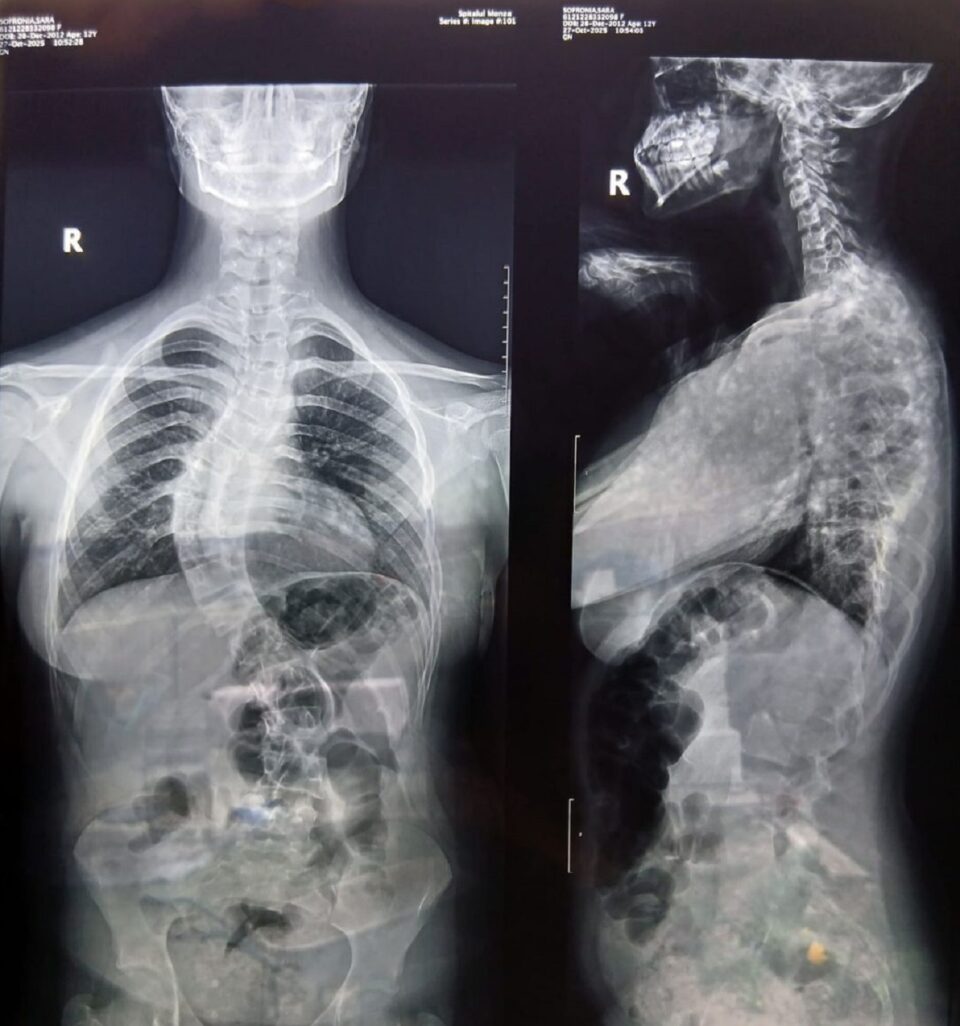

O adolescentă în vârstă de 13 ani, Sara Sofronia, are nevoie de o operație care îi poate schimba viața. Ea se luptă cu o afecțiune severă, scolioza, o deformare progresivă a coloanei vertebrale ce îi afectează nu doar postura, ci și respirația și, în timp, șansa la o viață normală.

Sara s-a născut în Italia, alături de sora ei geamănă, dar a revenit anul trecut în România, la Suceava, împreună cu familia, cu speranța unui nou început. La scurt timp, însă, durerile au început să apară, iar diagnosticul a venit ca o lovitură: o formă avansată de scolioză care necesită intervenție chirurgicală urgentă. Pentru că are mare nevoie de ajutor, familia Sarei a apelat la Asociația „Salvează o Inimă”, care a demarat o campanie umanitară.

Există o șansă reală pentru Sara. O intervenție chirurgicală complexă poate opri evoluția bolii și îi poate reda dreptul la o copilărie normală. Costul acestei șanse este de 36.400 de euro, o sumă imposibilă pentru o familie obișnuită, dar care devine posibilă atunci când oamenii aleg să nu rămână indiferenți.